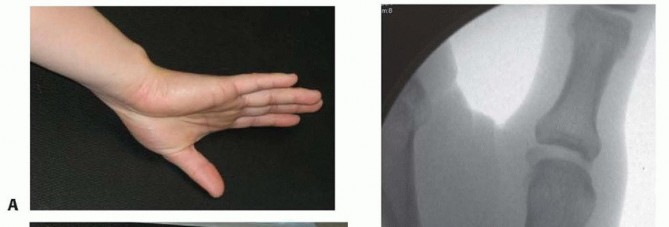

Clinical Evaluation and Diagnostic Imaging

The clinical evaluation must begin with a detailed history, focusing on the mechanism of injury, occupational demands, and hand dominance. Physical examination will typically reveal profound localized tenderness, swelling, and ecchymosis around the thenar eminence. Palpable instability or a visible "shelf" deformity at the CMC joint strongly suggests dorsal subluxation of the metacarpal shaft. A rigorous neurovascular examination is mandatory, with specific attention paid to the superficial radial nerve and the palmar cutaneous branch of the median nerve, both of which are at risk during surgical approaches to this region.

Our imaging protocol must be exhaustive to provide a three-dimensional understanding of the fracture morphology. Standard hand radiographs are insufficient due to the unique 30-degree pronated position of the thumb relative to the rest of the carpus. A True AP View of the Thumb CMC Joint (Robert's view) is obtained with maximal forearm pronation, placing the dorsum of the thumb flat on the cassette. This optimizes visualization of the joint space and the critical ulnar fragment. The True Lateral View (Billing and Gedda) is achieved with the hand pronated 20 degrees and the thumb flat on the cassette, with the X-ray beam tilted 10 degrees from vertical in a distal-to-proximal direction.